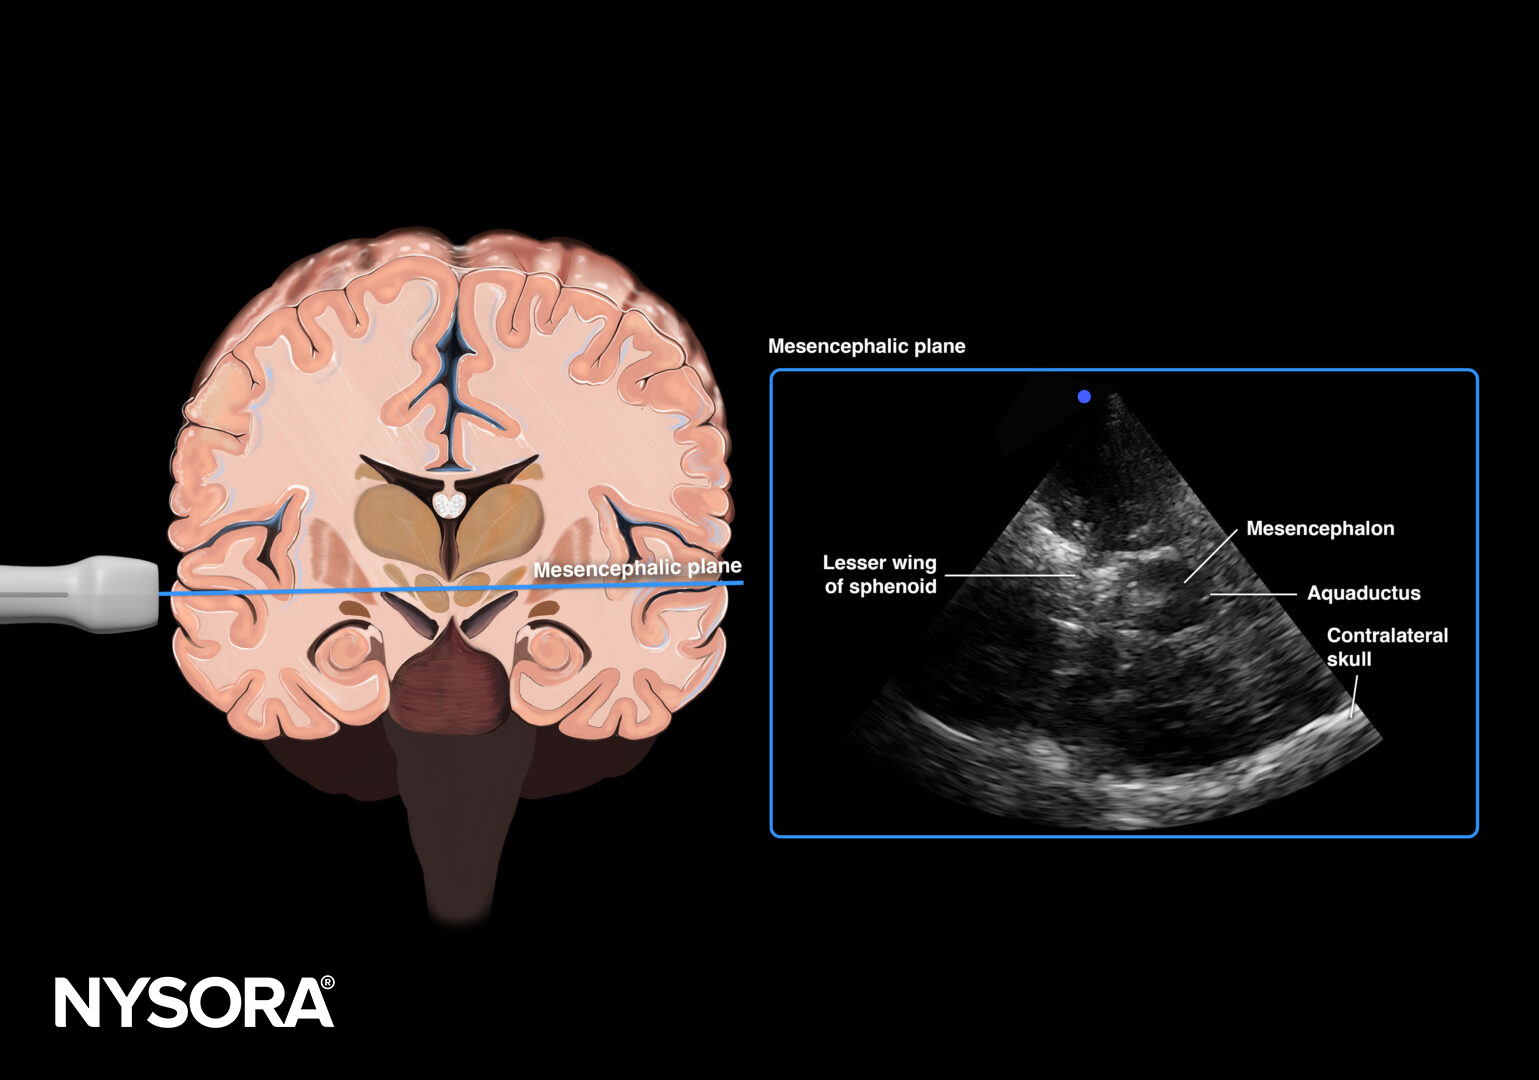

Transducer position for transcranial Doppler examination of cerebral circulatory arrest.

Mesencephalic plane.